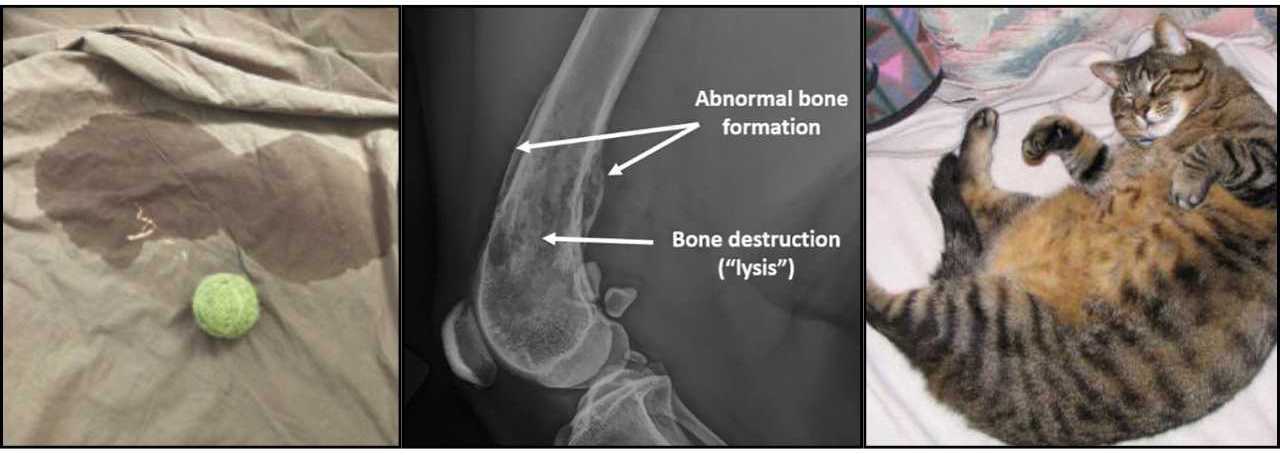

A follow-up study showed a two-fold increase in bone cancer in dogs that were spayed or neutered.

Another study found spayed female dogs had an eleven-times higher risk of developing brain tumors.